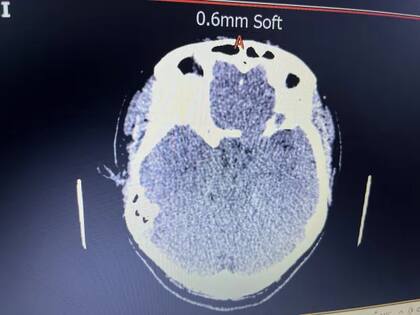

Por ese motivo, solicitó otra cita con la misma médica, quien le realizó una resonancia magnética. ¿El resultado? Devastador. Encontraron un tumor del tamaño de una pelota de tenis que empujaba el ojo hacia adelante. Le dijeron que debía pasar por una cirugía de urgencia.

“Estaba devastada y llorando por la noticia. En mi mente pensaba cómo se lo iba a decir a mis dos hijos. Los médicos me dijeron que mi tumor era complejo y, aunque estaba detrás de mi ojo, apenas tocaba mi nervio óptico, razón por la cual todavía tenía vista. Pasó desde la parte superior de mi cabeza, debajo de mi ojo y fue creciendo en mi cráneo”, reveló.

Cuando le hicieron otros estudios, finalmente le confirmaron que tenía un meningioma intraóseo. Tras la noticia, pasó por una operación de 10 horas y regresó a trabajar en marzo de 2023.

Ciaran, actualmente, se realiza escaneos anuales y tiene una placa de titanio que le reemplaza parte del cráneo. A pesar de su condición, supo salir adelante y se convirtió en el orgullo de los médicos.